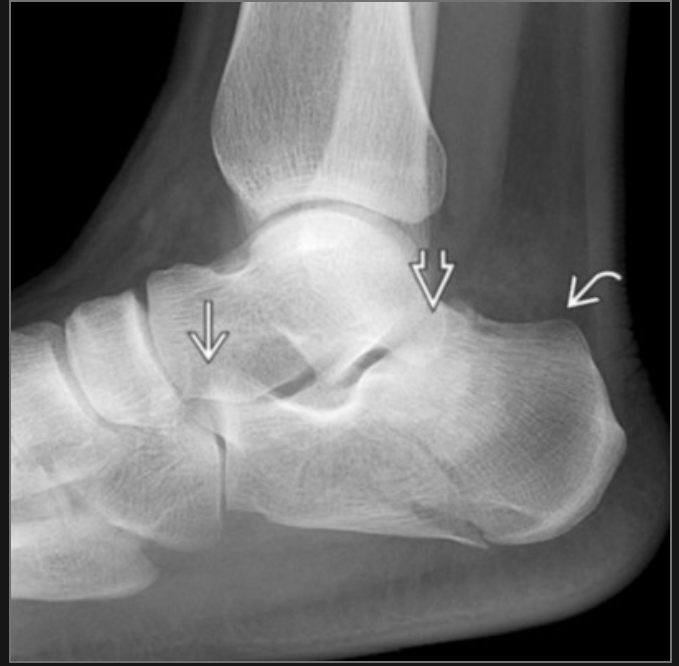

Haglund deformity

”pumps bump”

postero-superior calcaneus from high heels usually

how do we know if this fracture is intraarticular in extension?

Boehler angle is reduced (normally 20-40, here is 10)

CT can confirm (sanders classification)